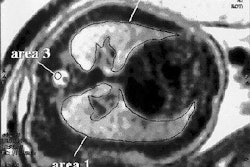

Both events crimped the firm's ability to raise cash, and the company struggled to remain viable until it negotiated a round of investment capital that put it back on its feet. The firm is now back in action with a new dedicated breast imaging gamma camera that it hopes will prove superior to scintimammography performed on whole-body SPECT units.